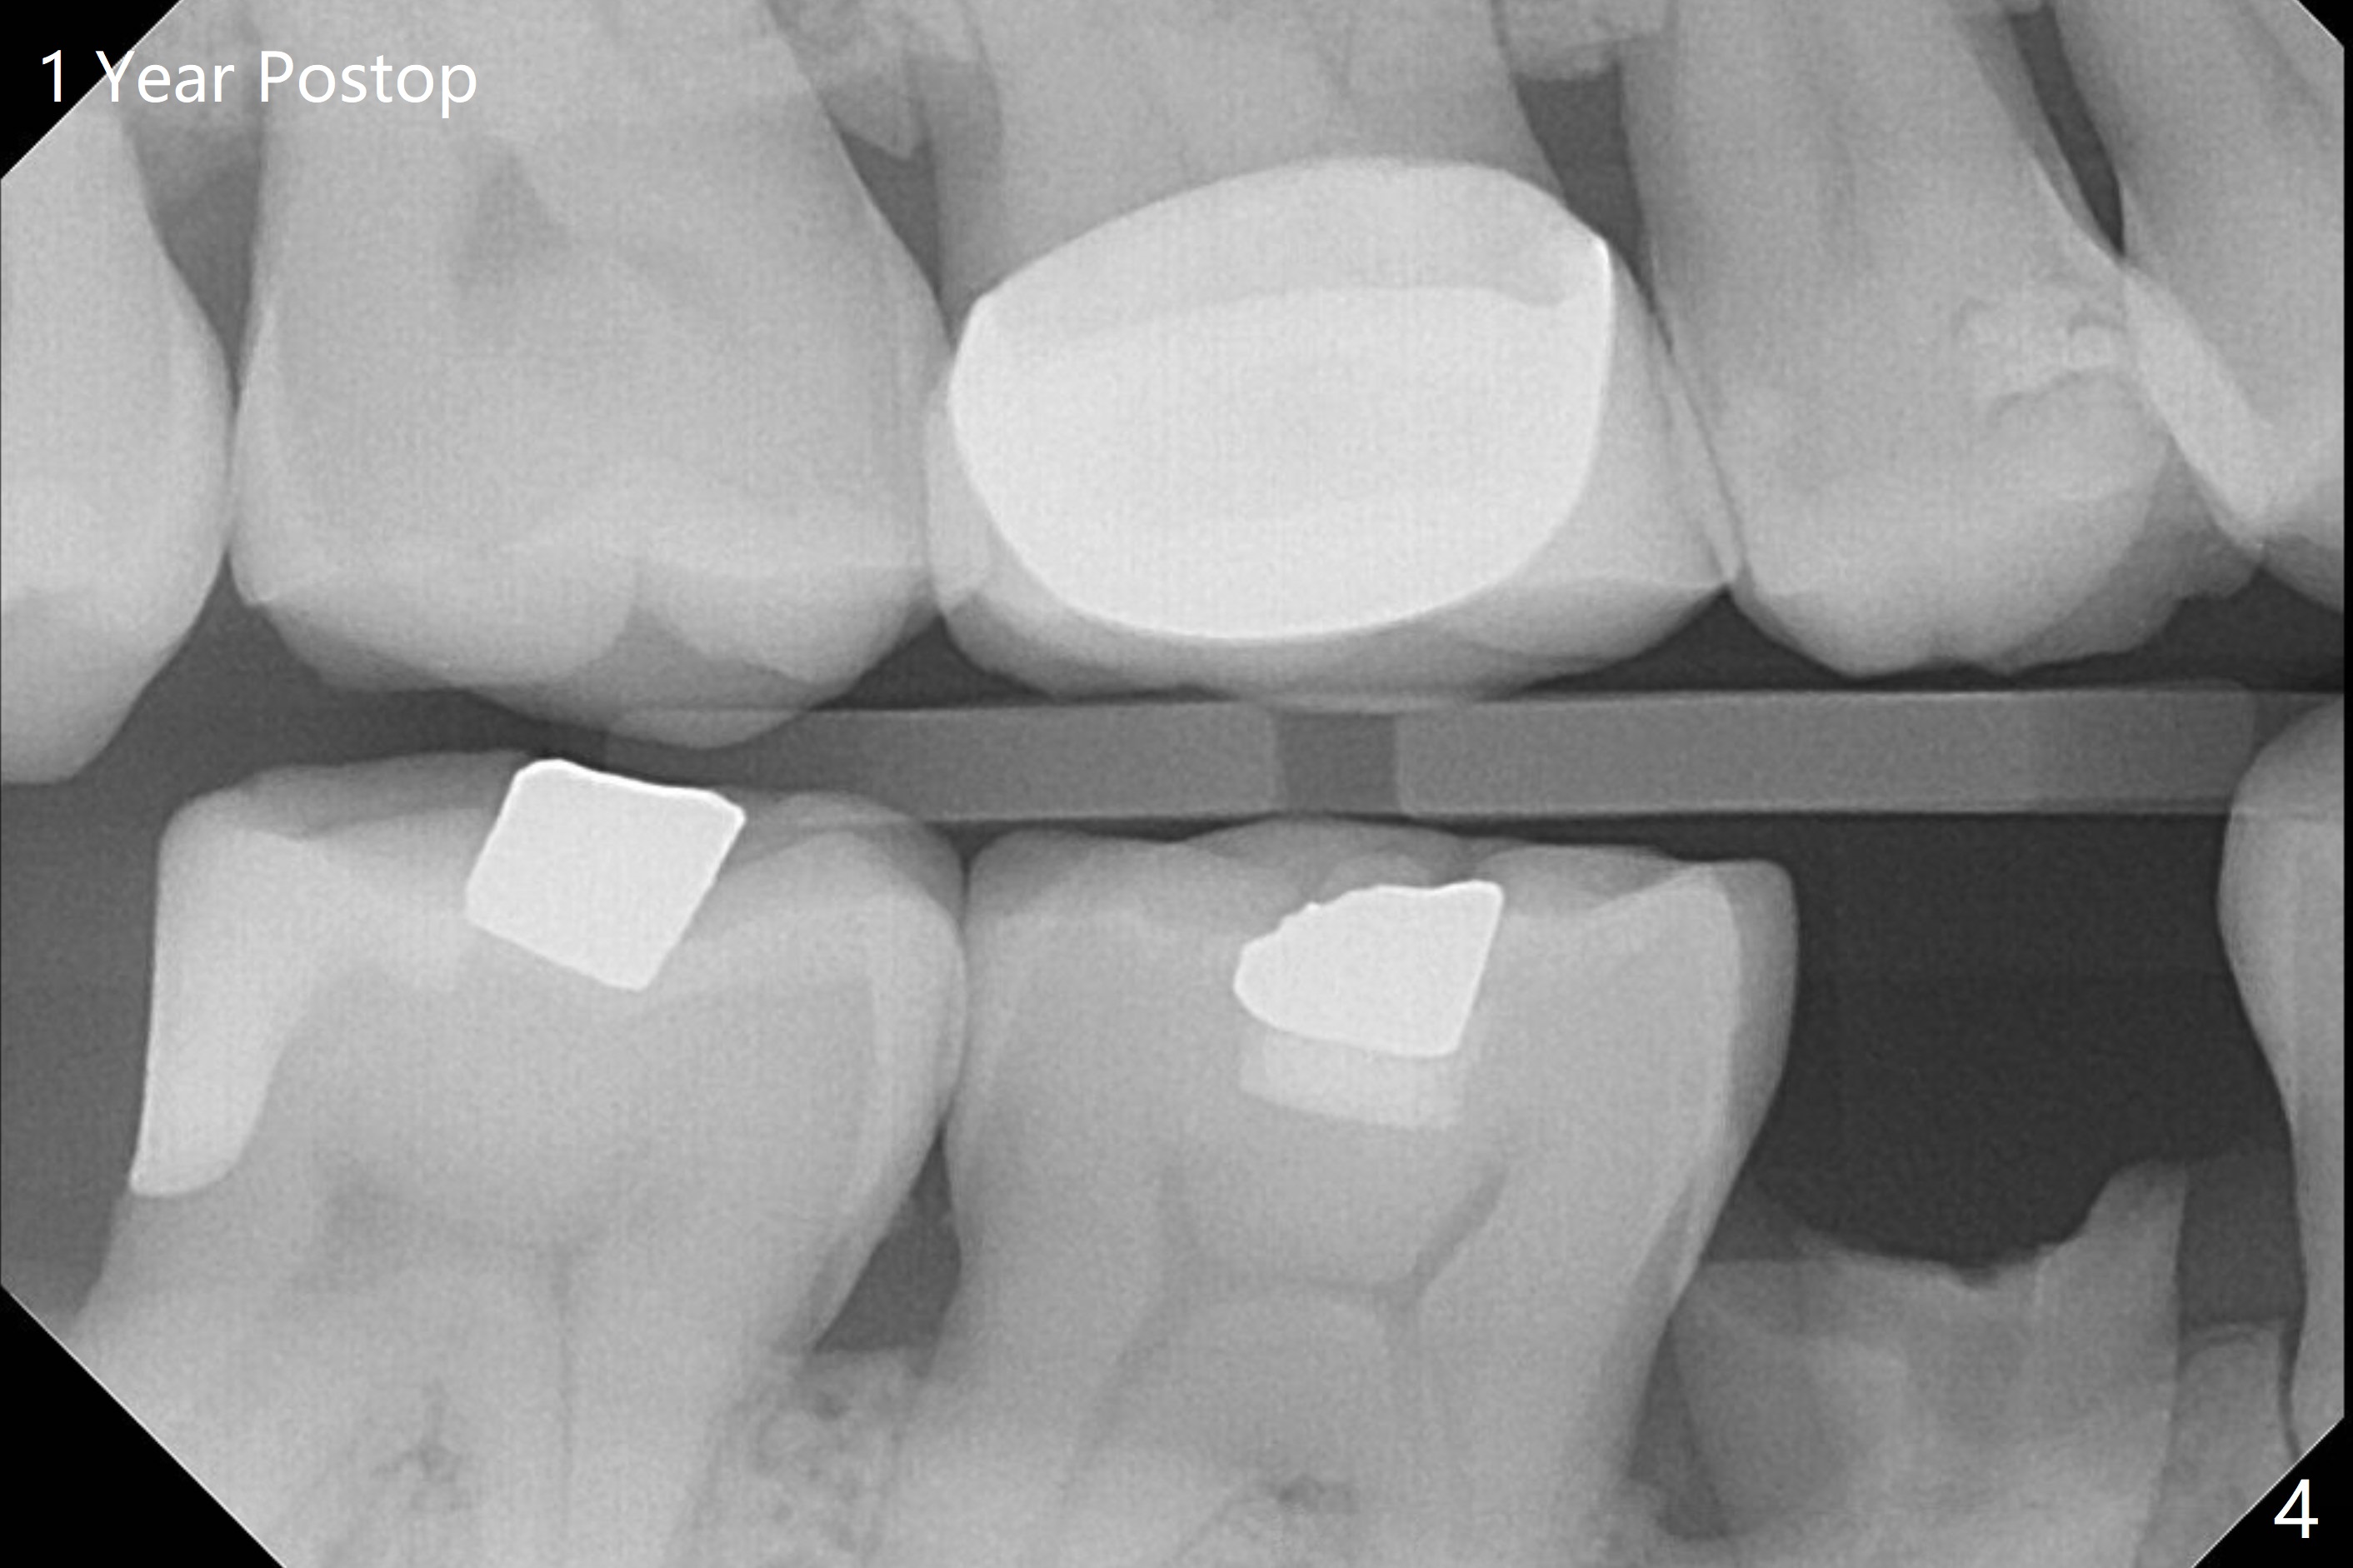

When the tooth #32 of a 47-year-old man is extracted, two pieces of 2x2 gauze (Fig.2 G) are inserted into the wound for hemostasis and composite is placed at #31 without compromise (Fig.2,3 *). Finally a 20x10 mm collagen plug is inserted into the socket of #32 prior to suturing to prevent Dry Socket. There is no leak or 2nd caries 1 year postop (Fig.4).